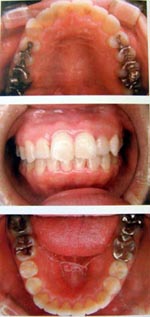

成人

顎が十分に成長せず、口の中が狭い状態

矯正後

十分い広がり、歯も自然な状態に整えます。

顎が小さく、口の中の空間が十分にない場合、いびきや睡眠時無呼吸症候群の原因になることがあります。

上記のような例で、症状が出ている場合、抜歯をせず口の中の空間を広くする装置を使用することで、症状をなくすことができます。